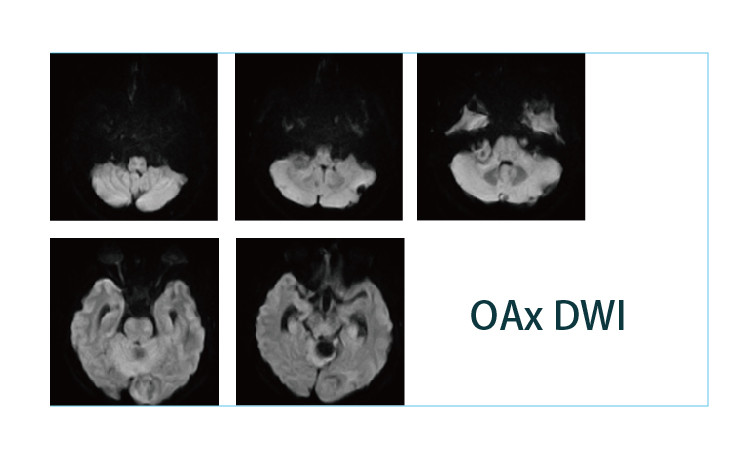

【朗润影像档案】磁共振影像病例分享(编号20190412)